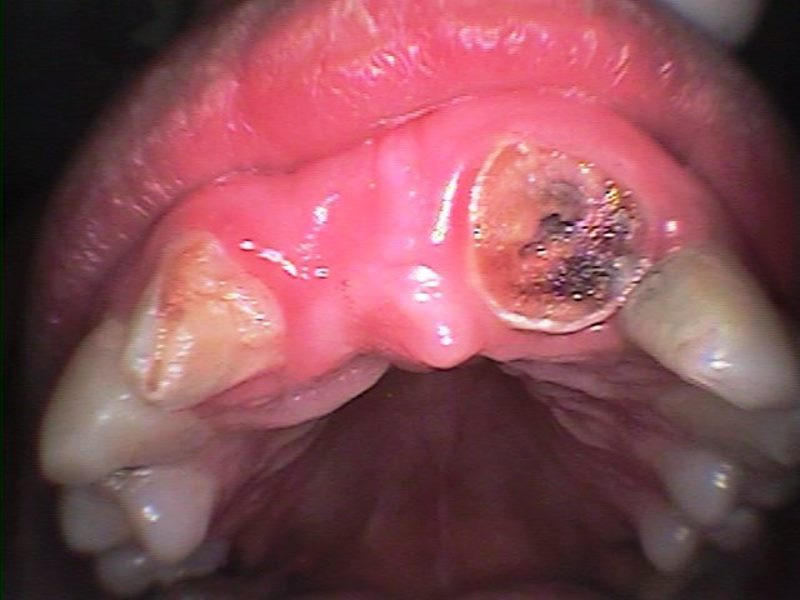

Vista oclusal inicial

Frente inicial se planifica rehabilitación de frente estético combinando endodoncia implante